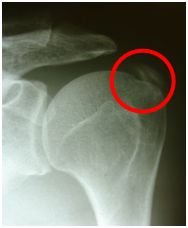

The pain can be so severe that patients often attend accident and emergency for pain control. The diagnosis is usually confirmed by plain X-ray. After an episode of severe pain a more chronic pain can persist, which is similar to shoulder impingement, with pain in the outer arm affected by activities away from the body.

X-ray showing calcific deposit in supraspinatus tendon.